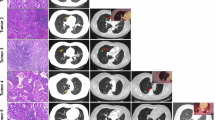

We identified ten patients from medical records at Massachusetts General Hospital (MGH) who had surgery between 2004 and 2019 for multiple early stage, spatially distinct, lung adenocarcinomas, with at least one specimen positive for the EGFR mutation by routine clinical genotyping (Table 1, patients 1–10). No patient had received any treatment before surgery and none was found to have lymph node involvement or suspected metastatic disease. Four patients were never smokers, three had a remote smoking history of <5 pack-years and three had a former >30-pack-year smoking history. None of the ten patients had a family history that was considered remarkable for multiple malignancies, including lung cancer. Tumor diameters ranged from 0.3 cm to 3 cm. In five patients, multiple tumors involved bilateral lungs, whereas, in three patients, tumors arose within different lobes on the ipsilateral side and, in two, they were confined to a single lobe (Table 1, Supplementary Table 1 and Extended Data Fig. 1a). Histologically, they were classified as precancerous atypical adenomatous hyperplasia (AAH, two tumors from two cases), adenocarcinoma in situ (AIS, one case), minimally invasive adenocarcinoma (MIA, ten tumors from six cases), mixed AIS and MIA (one case) and invasive adenocarcinoma (seventeen tumors from eight cases). In addition to the above cases of sporadic lung cancer, we applied our molecular analyses to a family with known germline transmission of an EGFR T790M allele (noncritical clinical features in the family history have been changed to preserve confidentiality) (Table 1, Fig. 1a and Extended Data Fig. 1b)23. In this family, the number of tumors per individual mutation carrier ranged from 1 to 13, with histology ranging from AIS to invasive adenocarcinoma (Fig. 1b,c and Supplementary Table 1). We first validated our tumor molecular analyses in one patient from this family with known germline susceptibility and then applied the same analytics to the sporadic cases with multiple primary tumors.

a, Pedigree of a family with multiple cases of lung adenocarcinoma, in which the index case (III-1) was diagnosed with six primary carcinomas (first resection), followed by resection of seven tumors 10 years later. Individuals shown in black have a confirmed or obligate germline T790M-EGFR mutation and those who have developed lung adenocarcinoma are denoted LUAD. The pedigree was minimally altered to preserve confidentiality (males, square; females, circles). b, CT scans of two tumors from patient III-4, one in the right middle lobe (RML) and the other in the right lower lobe (RLL). c, Histology of tumors from T790M-EGFR family patients showing the range of invasiveness encountered in our cohort, from precancerous AAH (patient III-4 lesion T2), to AIS (patient III-4 lesion T2), to MIA (patient III-1 lesion T2), to invasive adenocarcinoma (patient III-1; lesion T12). Panels are at ×40 magnification, with insets at ×200. Scale bars, 1 mm. d, Schematic of the tumor locations in patient III-1, at the first resection (left) and the second resection 10 years later (right). e, Copy number data for two tumors from the first resection of patient III-1. f, Phylogenetic lineage tracing of multiple tumors from patient III-1 based on WES. The tumors from the first resection, T1–T6, share no mutations outside of EGFR, as represented on the tree by no intersection point for clones 1, 6, 7, 12, 13 and 14 and, in the pie charts, by no colors shared between them. In contrast, the tumors from the second resection, T7–T13, share 29 mutations, as represented by the long trunk leading from cl1 to cl2 before branching into cl4, -5, -8 and -10. In addition, the pie charts for these tumors are complex mixtures of these four clones and clones are shared among multiple tumors. Numbers on branches are mutations that accumulated between two nodes, which represent distinct clones identified by WES. Numbers in parentheses are exonic mutations that are not in the FFPE context.